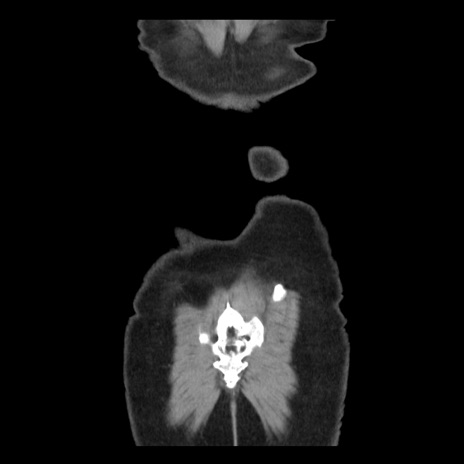

症例10(冠状断像)

横断像

矢状断像